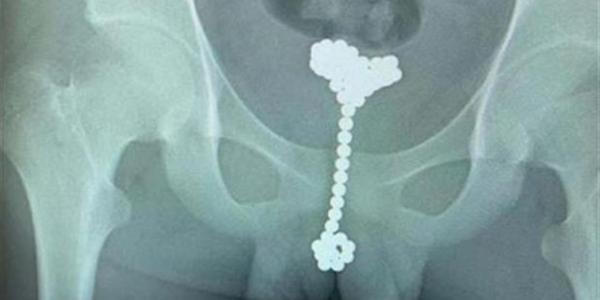

Dos jóvenes se introdujeron 84 bolas magnéticas por el pene para explorarse

• bolas magnéticas